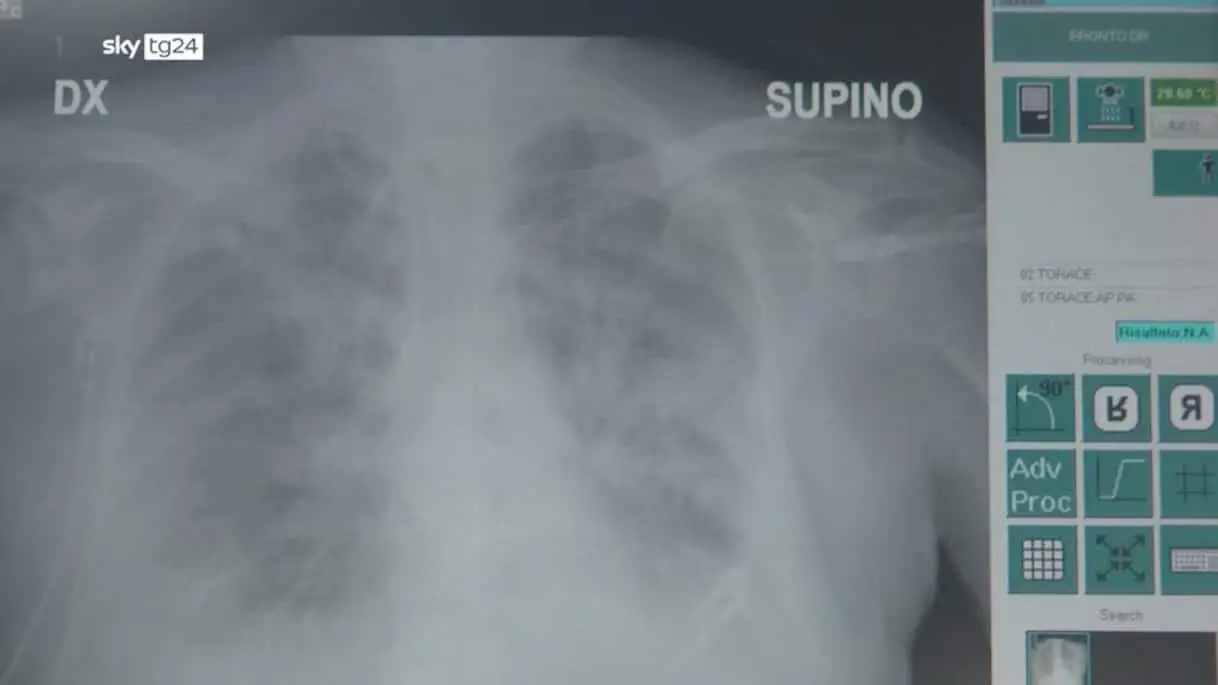

Polmonite interstiziale, di cosa si tratta e chi è a rischio